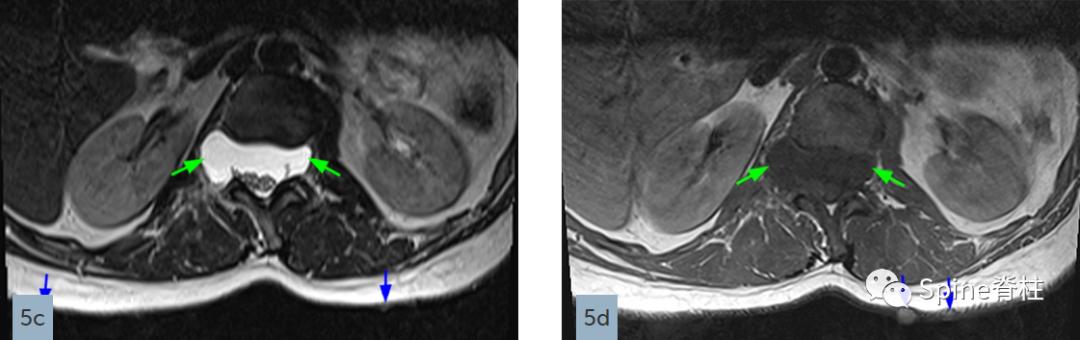

强直性脊柱炎患者L4-5水平的横断面T2(上图)和矢状位T2(下图)加权像提示多发性蛛网膜憩室(arachnoid diverticula)以及椎板和棘突的侵蚀(红色箭头),但需注意憩室周围的神经根粘连